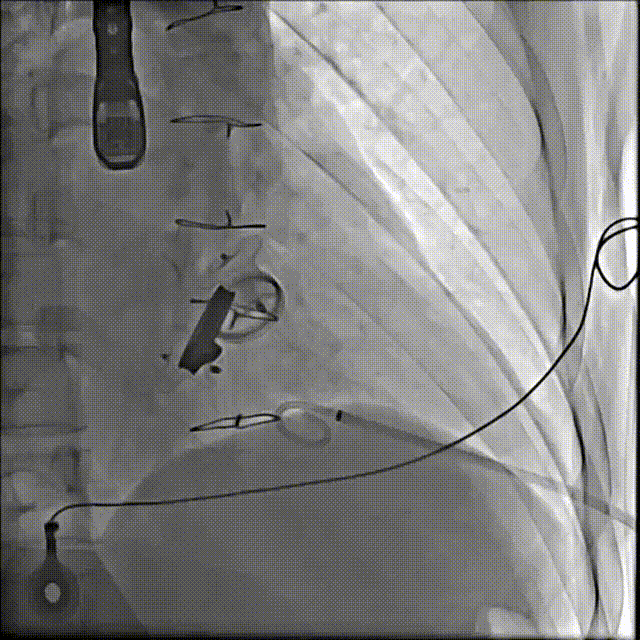

手术操作

3.选择7F鞘管通过1-2点位置瓣周漏,彩超显示鞘管对瓣周漏口的影响较小,结合漏口大小,选择14-16mmPDAO封堵此处漏口。